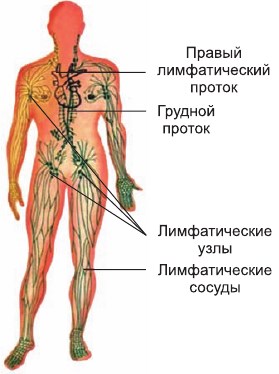

Изображения и схемы: как выглядит лимфа